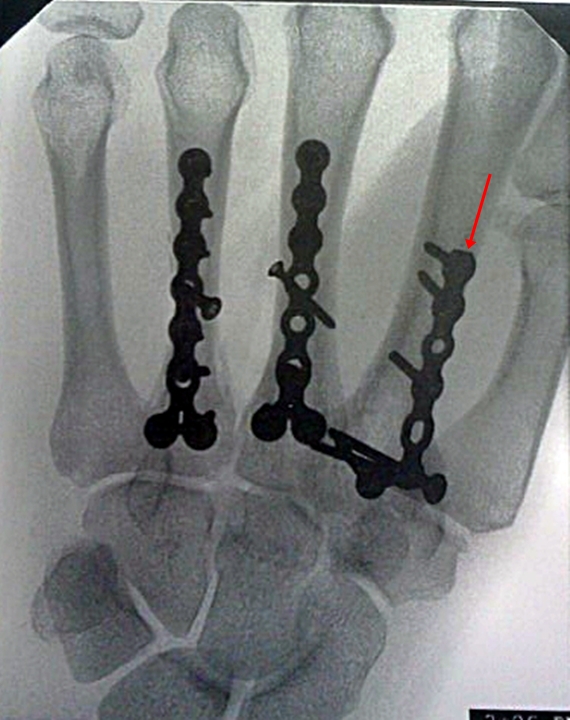

"back out" for some reason and is now protruding up on the back of my hand. Because it doesn't feel so good--just an odd deep ache, especially when I accidentally bump it on something and the plate is starting to move it must come out. Here's a different view before the screw started to move. Count them. Twenty screws. But only that one little stinker is loose--as far as the doctor can tell.

The question for me has been whether to take out all of the hardware while we are at it--which requires slightly longer surgery, a bit longer healing and an additional 3 inch scar on the back of my hand--not to mention a greater risk of upsetting my hand. Or just to remove the plates and screws on the one bone. Hmmmm. I still haven't decided yet.